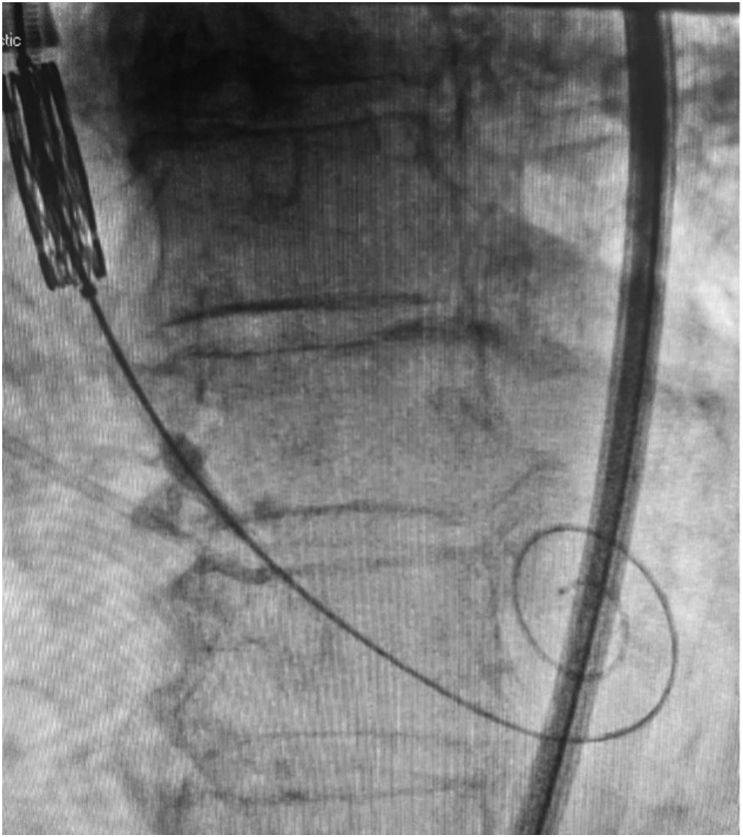

Desired fluoroscopic appearance of LV guidewire. Demonstrates compressed appearance in systole suggesting “snug” position in the LV apex. This position is best confirmed on echocardiography, where possible.